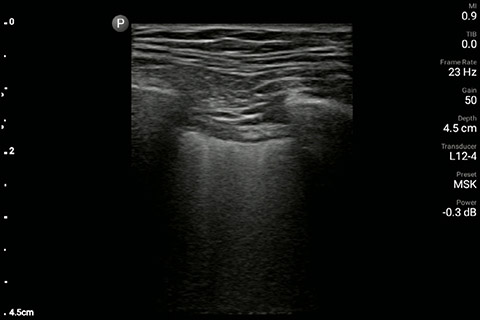

The patient had reduced LV systolic function without new or severe valvular pathology, a dilated, non-collapsing IVC, and diffuse B lines (left greater than right) on lung ultrasound imaging.

Lung image of the left chest

Lung image of the right chest